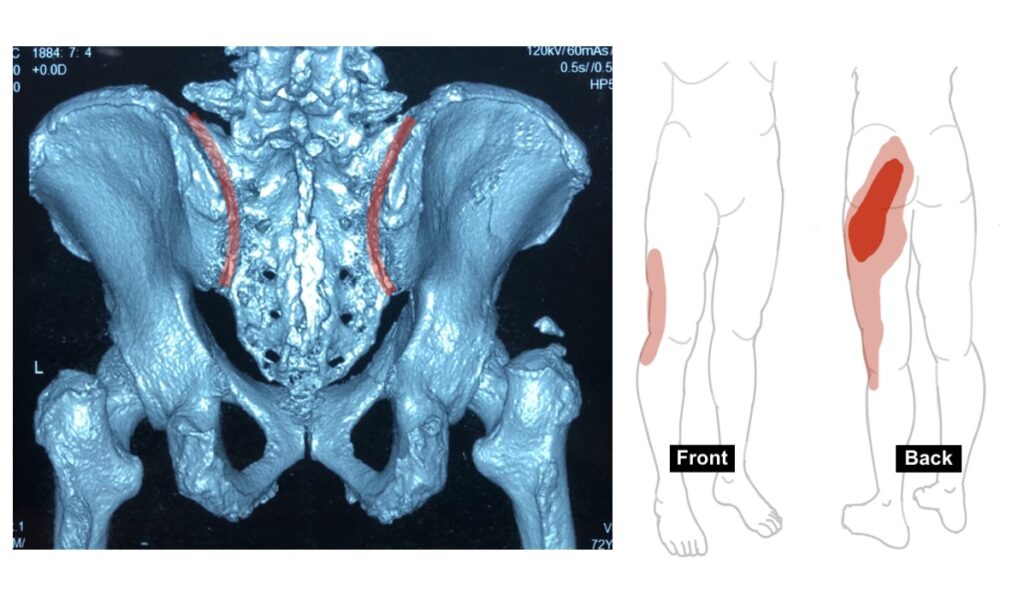

5. Sacroiliac (SI) Joint Pain

The pain usually felt around the buttock. It is more common among middle age female. The risk factors for developing this condition includes pregnancy, normal delivery, leg length discrepancy, previous trauma, previous spine surgery and aging process. Patient usually having difficulty in sitting long. As X-ray and MRI scan usually not helpful in the diagnosis, an injection of local anesthetics usually confirm the diagnosis of SI joint pain.